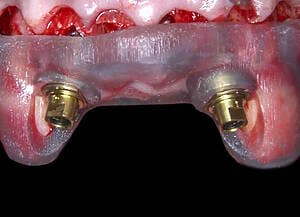

Natalie’s treatment began with a comprehensive clinical assessment, including a review of her medical and dental history, a full examination, and analysis of her functional difficulties such as her tongue habit and altered bite. A 3D cone-beam CT scan was then taken to assess bone quality and volume, identify areas of infection, and map important anatomical structures to ensure safe implant placement.

All data were transferred into digital treatment planning software, allowing virtual placement of implants and collaboration with the dental laboratory before surgery. This enabled careful evaluation of long-term outcomes and ensured the design of provisional and final prosthetics could be completed with precision. Following these discussions, the decision was made to proceed with the Fixed-Teeth-in-a-Day approach using the All-on-4 technique.

Surgical phase